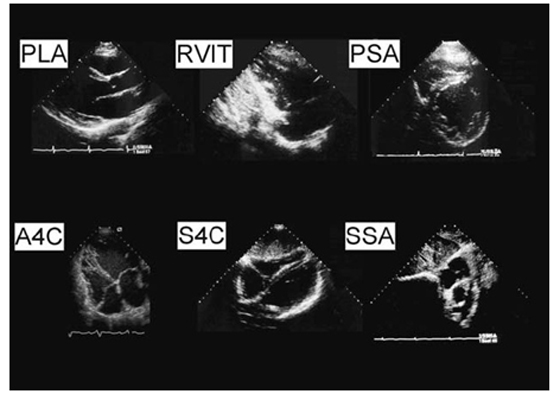

Такой же подход может быть применен к ПЖ. ПЖ должен изучаться в множественных проекциях и только в таком случае можно оценивать функцию ПЖ. К сожалению, во многих ЭхоКГ исследованиях оценка ПЖ ограничивается четырехкамерной проек-цией из верхушки. Однако рутинное двухмерное ЭхоКГ исследование ПЖ включает указанные в таблице и рисунке проекции.

Рисунок. Стандартные сечения для двухмерной ЭхоКГ оценки ПЖ:

PLA – парастернальное сечение по длинной оси, RVIT – приносящий тракт ПЖ, PSA – парастернальное сечение по короткой оси, A4C – апикальное четырехкамерное сечение, S4C – субкостальное четырехкамерное сечение, SSA – субкостальное сечение по короткой оси